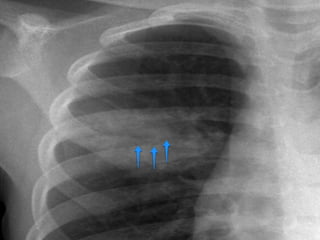

Air Bronchogram

A tubular outline of an airway made visible due to the filling of the surrounding

alveoli by fluid or inflammatory exudates

Conditions in which air bronchograms are seen:

• Lung consolidation

• Pulmonary edema

• Non-obstructive pulmonary atelectasis

• Interstitial disease

• Neoplasm

• Normal expiration

Air Bronchogram A tubularoutline of an airway made visible due to the filling of the surrounding alveoli by fluid or inflammatory exudates Conditions in which air bronchograms are seen: • Lung consolidation • Pulmonary edema • Non-obstructive pulmonary atelectasis • Interstitial disease • Neoplasm • Normal expiration

• #10 Bronchi, which are not normally seen, become visible as a result of opacification of the lung parenchyma. Branching, tubular lucencies of bronchi are seen in an opacified lung (Fig. 1a). This sign shows that the pathology is in the lung parenchyma itself (1). This sign is most frequently encountered in pneumonia and pulmonary edema. Its generalized form can be seen in respiratory distress syndrome (2). The air bronchogram sign shows that the central bronchi are not obstructed; however, it can also be seen when a mass causes half-obstruction. Bronchioalveolar carcinoma, lymphoma, interstitial fibrosis, alveolar hemorrhage, fibrosis due to radiation and sarcoidosis can also present with this sign (1–3). This sign can also be seen on CT images (Fig. 1b).

• #13 Bronchograms in RDS.